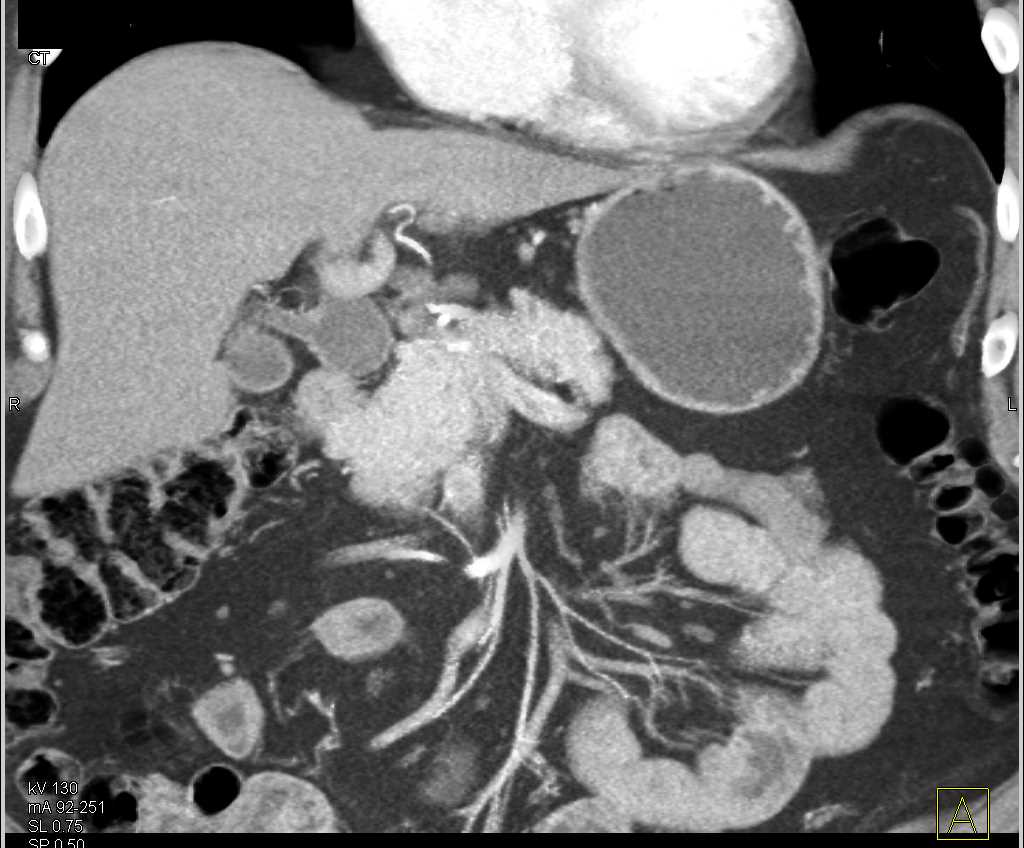

Professors Satomi Kawamoto and Professor Elliot K. Fishman (@ctisus), Associate Professor @LindaChuMD (@LindaChuMD), and Research Fellows Mohammad Yasrab and Juan Felipe Lopez-Ramirez (@FelipeLopezMD), presented an educational exhibit on βThe Challenges in the Detection and